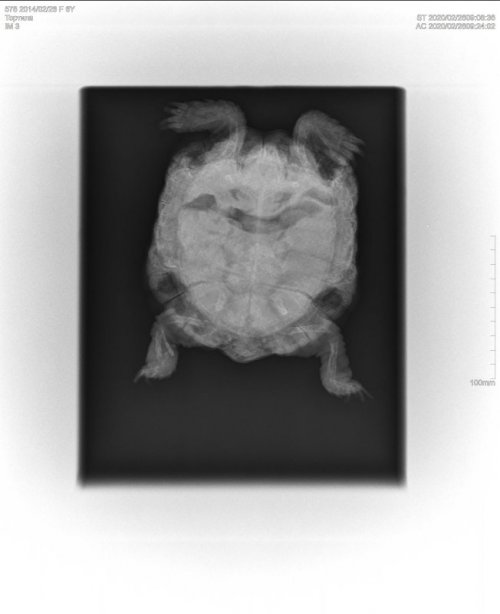

Podolnyi Ваше имя: Подольный Константин Локация: Украина, Днепр Опубликовано: 26 февраля 2020 Опубликовано: 26 февраля 2020 @Лилия116 на рентгене видно плохо все (параметры снимка выше нужно было делать). Есть газы в переднем отделе, что аж пожимает сердце. Скорее всего стаж в жкт и там много кала. И ещё, у черепахи очень мала плотность костей и сломана голень. каково состояние сейчас?